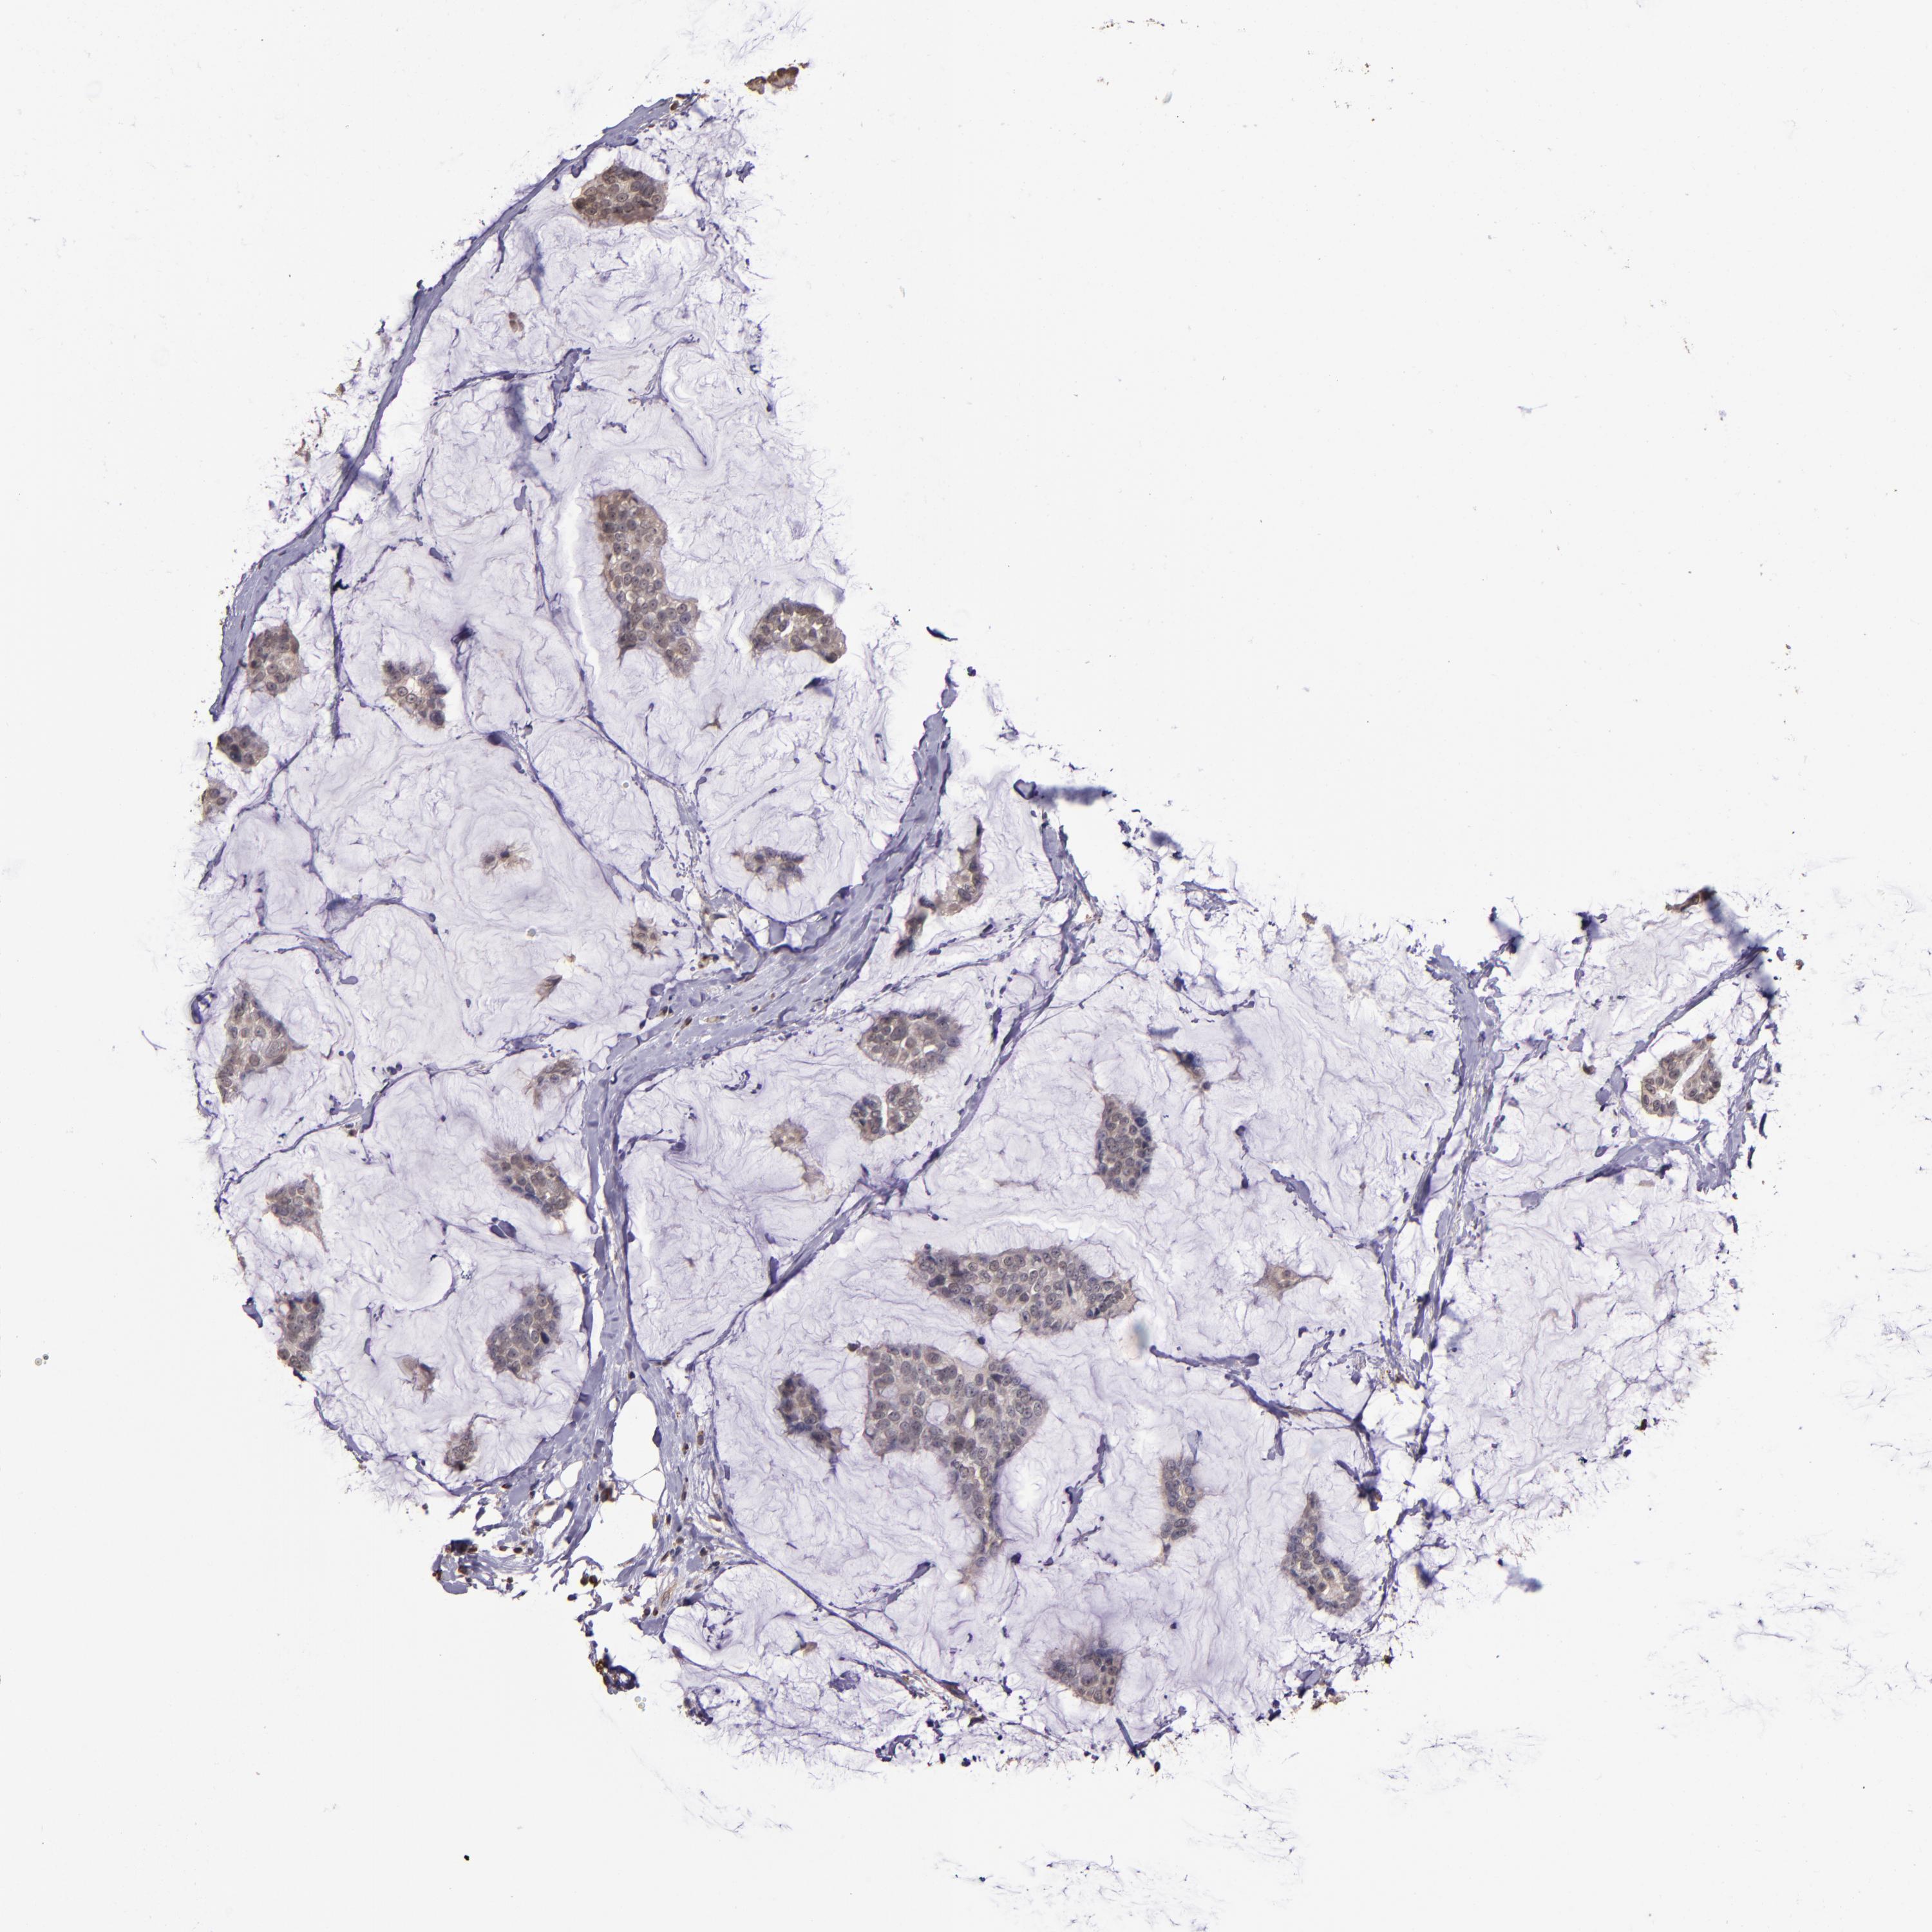

CANCER BREAST CANCER Show tissue menu

BRCA TCGA BRCA VALIDATION PROTEIN EXPRESSION

Breast cancer

Human cancer